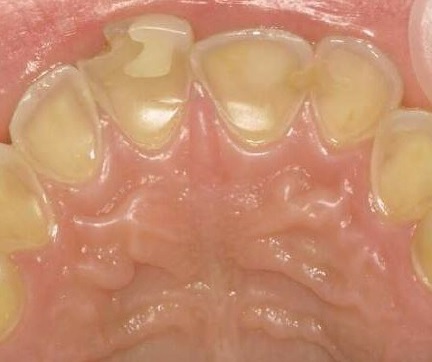

Farvestoffer til afsløring af plak på tænderne. Selv efter tre uger uden tandbørstning er der plakfri områder. Et område uden plak er et cariesfrit område. Med regelmæssig brug af tandbørste og tandtråd er det muligt helt at fjerne cariestruslen. Kun steder hvor plakken ikke fjernes regelmæssigt kan der opstå caries. I naturen er det den grove kost der fjerner plakken. Glatte tandoverflader er en evolutionær genistreg, der letter plakfjernelsen på de flader der udsættes for mindre slid. Formålet med regelmæssig plakfjernelse er at få fjernet plakken fra de tandoverflader, hvor almindelig tygning ikke fjerner plakken (plak-stagnations-områderne). (Else Theilade).